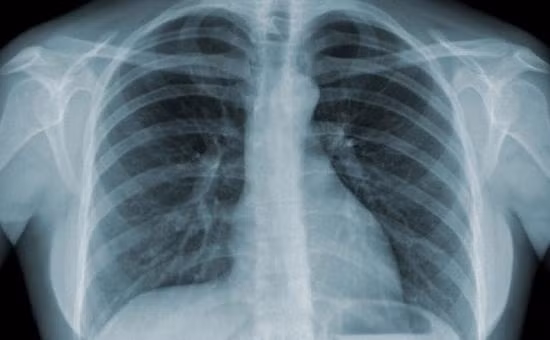

Phim chụp một nạn nhân bị lao phổi. Ảnh minh họa

Chủng vi khuẩn gây ra bệnh lao phổi đã được tìm thấy trong các xác ướp Ai Cập cổ đại, chứng tỏ rằng đại dịch này đã từng hoành hành trên Trái đất cách đây hàng ngàn năm.Bệnh lao phổi do một loại vi khuẩn phát tán trong không khí gây nên, và nó tấn công vào phổi của con người, gây suy yếu các cơ quan nội tạng, đau ngực, đổ mồ hôi đêm và ho dữ dội.